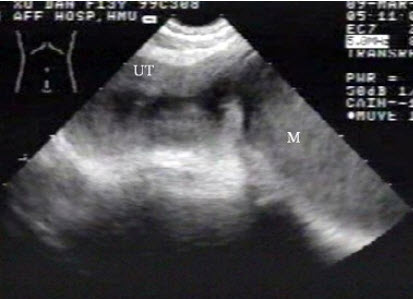

[单选题]女性,62岁,1周前疑诊为宫颈癌。超声检查如图,最可能的诊断是()A . 子宫肌瘤B . 宫腔积液并感染C . 子宫内膜癌D . 子宫内膜炎E . 正常声像图